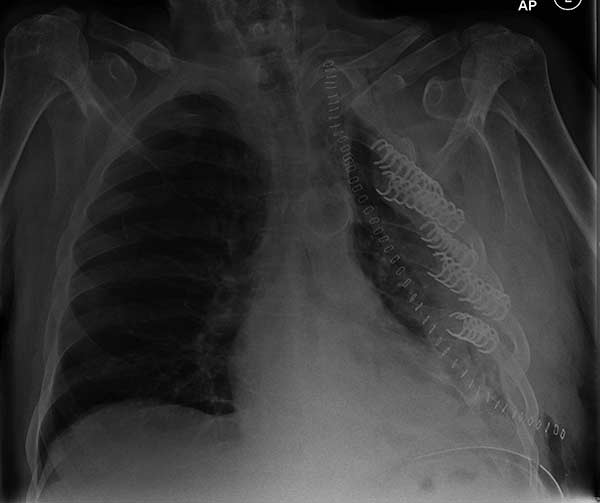

- Fixation of massive chest wall injury (Figures 9-11)

Many different methods have been proposed to stabilize the chest wall after resection. The rigid reconstruction of chest wall defects with GORE-TEX® felt or mesh-cement sandwiches has been widely reported. However, it does not restore normal chest wall mechanics and is vulnerable to catastrophic prosthetic infections. We believe that the application of these newer surgical materials is likely to provide important clinical benefits over established techniques. It is also an advantage that the same techniques can be applied to a number of clinical scenarios. We are particularly interested in their use in massive chest wall trauma, where early restoration of chest wall mechanical integrity may well play a part in reducing respiratory morbidity. We treated 9 patients (4 pectus corrections, 3 chest wall resections for malignancy, 1 flail chest fixation and 1 chronic pain syndrome from rib malunion) with excellent results.

At surgery, the mass was arising from the cortex of the third rib, and solid measuring 5x8 cm. There was no macroscopic involvement of the surrounding extra-thoracic musculature or of the underlying lung, the mass being confined to the rib and intercostal muscles. The patient underwent resection of the second to fourth ribs and the rhomboid muscle as well, in the attempt to get clear margin. The large antero-lateral defect was eventually reconstructed using 2 mouldable titanium bars. To prevent lung herniation through the defect, we reconstructed the layers anatomically using a biological patch (Veritas®). The final histopathology was a low grade sarcoma of the chest wall with clear resection margins.

He made an excellent recovery with daily physiotherapy to encourage shoulder movements. He was discharged with oral analgesia on postoperative day 4. At 1-month follow-up the patient had no pain at all, discontinued analgesia on postoperative day 17 and demonstrated a full range of shoulder movement. His chest x-ray was unremarkable and the wound healed without complication.